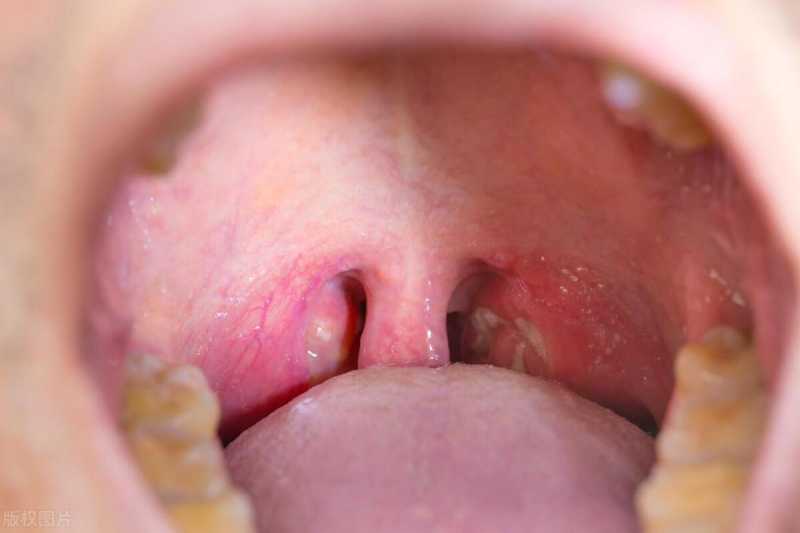

扁桃体与鼻窦:防御与脆弱的平衡

接下来,咱们聊聊扁桃体和鼻窦这两个小伙伴,它们可是身体里的重要防线哦!扁桃体雄踞呼吸消化交界,乃体内免疫防护之坚固堡垒。其迅速制造抗体与淋巴,坚决捍卫健康,有效抗击各类病菌病毒威胁。然而,当扁桃体反复发炎,成为慢性病灶时,手术切除成为必要选择。这样做啊,不光能让患者少受点罪,还能防止因为炎症拖太久,把免疫系统给整乱了套。